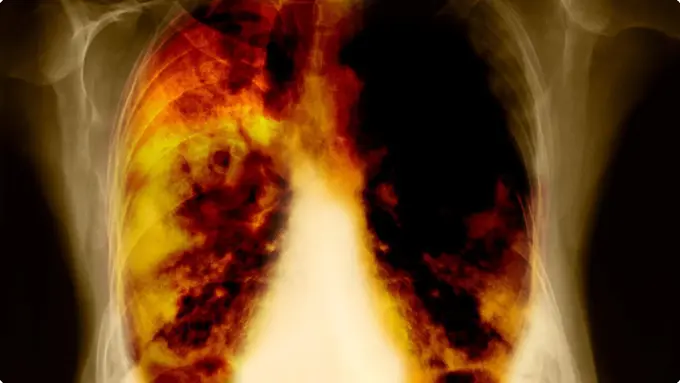

Fimela.com, Jakarta Penyanyi senior January Christy menghembuskan nafas terakhir pada Jumat (16/9/2016), sekitar pukul 00:45 di Bandung. Sebelum meninggal, penyanyi yang lahir pada 17 Januari 1958 ini memang diketahui sempat dirawat di rumah sakit karena penyakit kanker paru-paru.

Ya, penyakit paru-paru memang dapat menyerang siapa saja, tidak hanya pria, tapi juga wanita. Sayangnya banyak pasien yang terlambat memeriksakan diri karena mereka tak menyadari bahwa dirinya terkena kanker paru-paru. Dilansir dari Boldsky.com, ada beberapa gejala awal kanker paru yang harus disadari supaya bisa mendapatkan penanganan lebih dini.